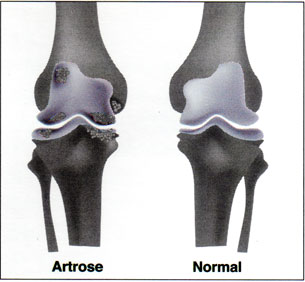

Artrose – Doença articular degenerativa

A Artrose é um distúrbio muito comum que afeta uma ou mais articulações, como por exemplo, quadril, joelho, mãos etc. O início ocorre com uma deterioração local da cartilagem articular, caracterizando-se pela degeneração progressiva desta cartilagem e deformação do osso subcondral e por inflamação secundária da membrana sinovial. Esse distúrbio é conhecido também pelos termos […]